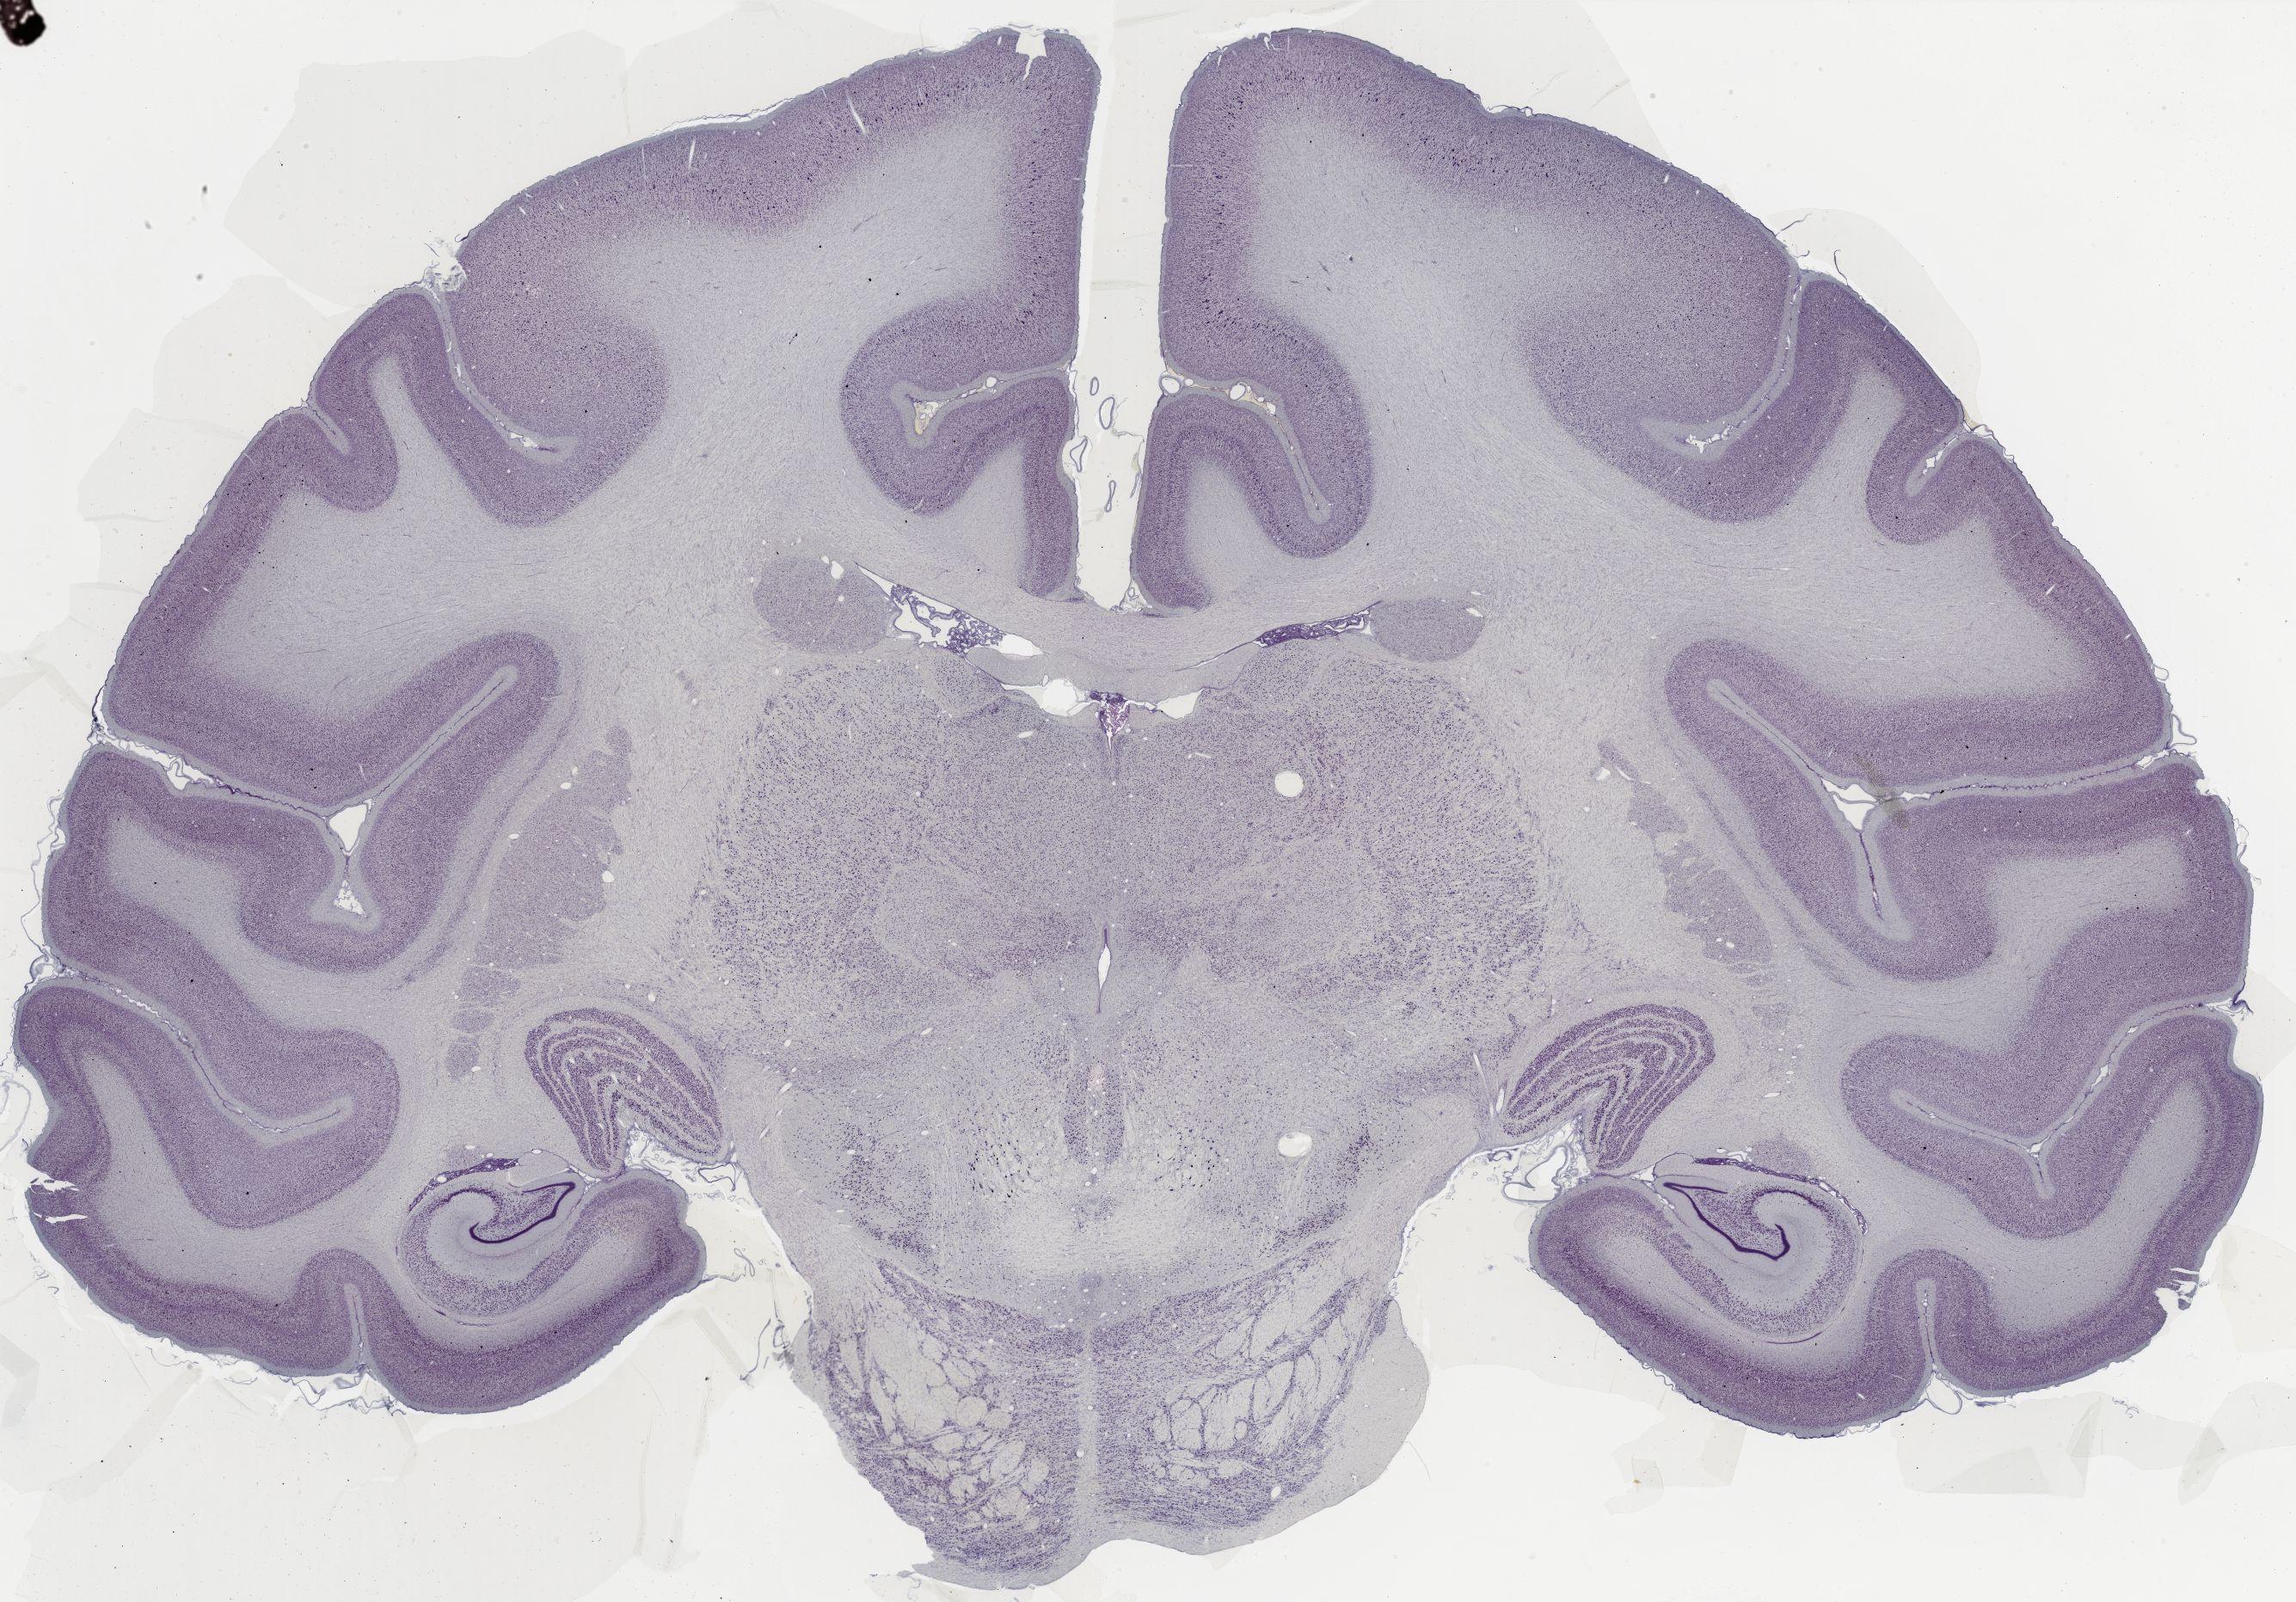

Datasets -> Macaca Mulatta -> Nissl, coronal, histo, Whole-Brain, adult [ Metadata ] · Source: Edward G. JonesDisplaying Sections 1 thru 40 of 56 Sections for this DatasetPages: 1 2 1339 - labeled 1301 - labeled 1251 - labeled 1201 - labeled 1151 - labeled 1102 - labeled 1051 - labeled 1040 - labeled 1020 - labeled 1006 - labeled 1001 - labeled 0982 - labeled 0975 - labeled 0958 - labeled 0951 - labeled 0941 - labeled 0924 - labeled 0920 - labeled 0901 - labeled 0894 - labeled 0878 - labeled 0875 - labeled 0859 - labeled 0851 - labeled 0845 - labeled 0824 - labeled 0823 - labeled 0801 - labeled 0800 - labeled 0785 - labeled 0781 - labeled 0771 - labeled 0770 - labeled 0732 - labeled 0721 - labeled 0720 - labeled 0701 - labeled 0682 - labeled 0680 - labeled 0666 - labeledPages: 1 2